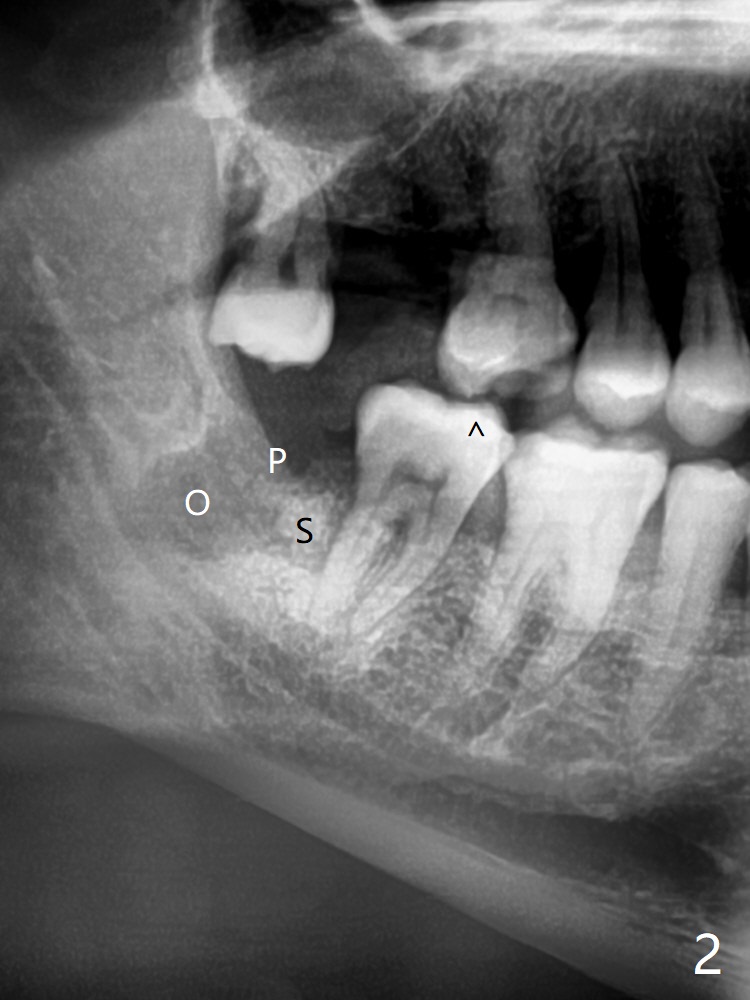

47岁男,牙周炎,吸烟(一天一包),忍受右下智齿(32)疼痛多天后来诊所要求拔除(中国老百姓认为疼痛期间不能拔牙, 图一),第二磨牙远中骨质吸收严重(*),植骨是必须的。为了顺利成骨(与方炳忠医生根管治疗之后调整咬合一致),拔除智齿前,对第二磨牙近中颊侧咬合面进行降低(图二:箭头)。为了止血和减少骨粉使用量,牙槽窝远中放置胶原骨(Osteogen Plug,O),而第二磨牙远中放置粘性骨粉(sticky bone (allograft),S),后者也是必须的,因为在炎症期间,拔除智齿,出血严重,一般骨粉容易被血冲走。下次植骨前牙槽窝必须放置含肾上腺素纱布止血。最后牙槽窝表面放置两块PRF膜(P),严密缝合。术后服用Amoxicillin, Medrol Dose Pak and Tylenol III。